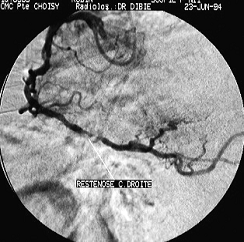

a)

b)

c)

d)

Figura

Figura 7. Coronarografie stanga a), dreapta b) stenoze multiple ateromatoase